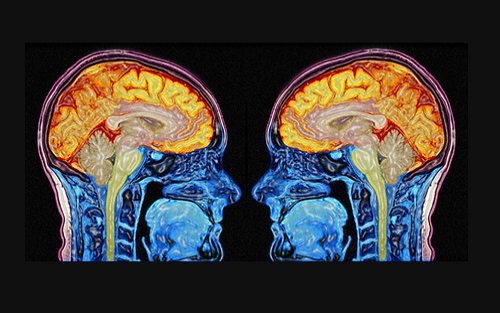

虽然,这些发现对医学的重要性仍不明确,但是ENIGMA联盟称,一种新型分布式计算方法可以通过大量的MRI扫描图像和DNA测试结果对其进行排序。组织此次研究的神经学家保罗·汤普森说:“Enigma联盟目前的工作是将每个扫描图像的像素相结合,然后与每一个基因组进行比对。这是此工作的方法图。”

保罗·汤普森是南加州大学基因影像学中心负责人,他相信Enigma联盟是研究人类大脑的最大的研究机构。近日,《自然》杂志上刊登了一项最新研究,列出了287位作者,193个机构。此研究对30717人的大脑MRI图像以及由柬埔寨、南非、美国等国的研究人员收集的DNA信息进行分析。

Enigma联盟对年龄在9-96岁之间的人的大脑进行MRI扫描,花费3000万美元(每个大脑扫描费用约1000美元)。通过将扫描图像与这些人的DNA进行比对,Enigma联盟研究人员表示发现了8个影响大脑整体大小或各分区大小的基因。